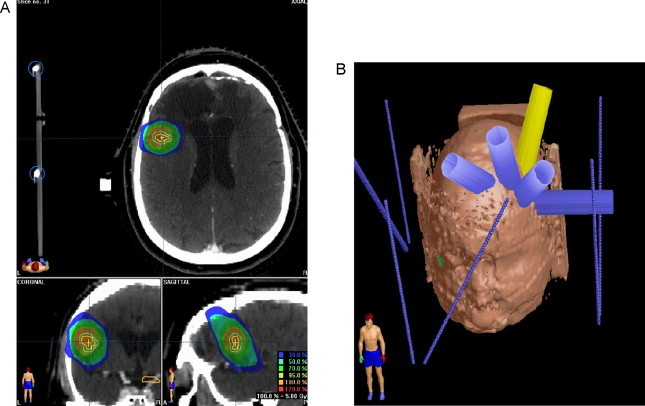

The recurrence was treated in January 2007 using a Varian Clinac® 600 stereotactic system with a BrainLAB mask. A total dose of 25 Gy was delivered in 5 Gy per fraction with 6-mV photon. Gross target volume (GTV) was outlined according to MRI images, and a 5-mm margin was added to define CTV plus 2 mm to perform the planning target volume (PTV). Critical organs and structures including the optic chiasm, brainstem, eyes and left optic nerve were contoured. Dosimetric characteristics are shown in Table 1 and Fig. 3.

Fig. 3.

Treatment plan and dosimetric characteristics. (A) Dosimetric characteristics in relapse area and (B) treatment plan.